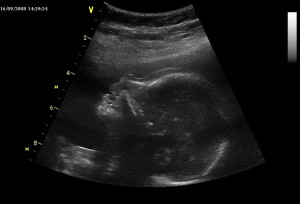

Tento detail hlavičky je už z 16.9. Nosánek prý mám po mamince, říkal pan doktor :o)